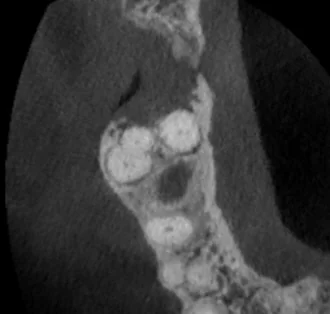

What the CBCT Showed

The 3D imaging revealed several findings that didn't fit a routine endo-perio presentation: calcification within the canal, furcation involvement, and — most concerning — irregular bone borders with cortical plate erosion. The borders weren't smooth the way you'd expect with a standard infection or cyst. They were ragged and ill-defined, which in rare cases can indicate malignancy.

Our working differential included a combined endo-perio lesion, a vertical root fracture, and — given the irregular CBCT borders — possible maxillary sinus carcinoma. Sinus malignancies account for less than 0.2% of maxillary sinus pathologies, but the cortical plate erosion pattern on this CBCT was not something we could ignore.

• Irregular CBCT Borders Are a Red Flag: Smooth, well-defined radiolucencies suggest infection or cysts. Ragged, ill-defined borders with cortical plate erosion should raise suspicion for malignancy and warrant further investigation.